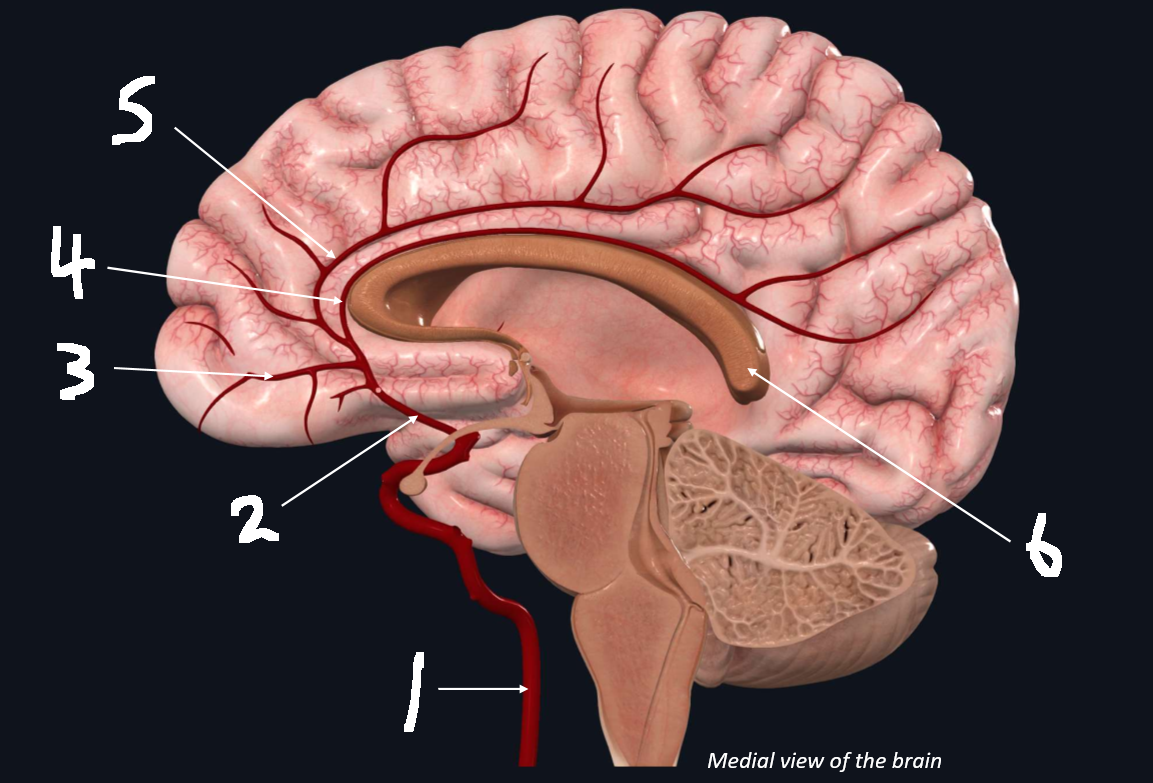

What is 1?

internal carotid artery

What is 2?

anterior cerebral artery

What is 3?

frontopolar artery

What is 4?

pericallosal artery

What is 5?

callosomarginal artery

What is 6?

corpus callosum